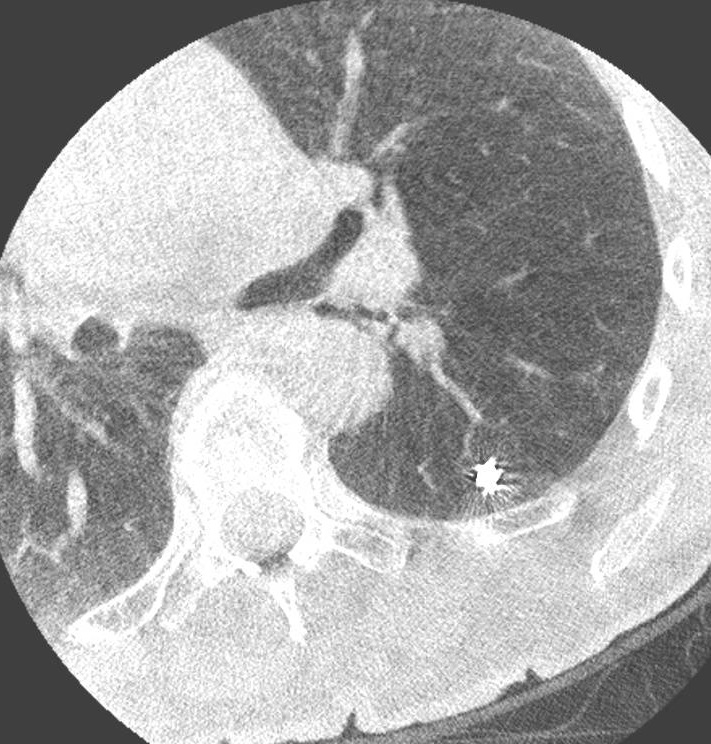

A woman with a confirmed left lower lobe adenocarcinoma presented an additional 3 mm nodule in the same lobe, too small for percutaneous sampling. Its nature was unknown, yet its location was directly relevant to surgical planning: if malignant, resection would need to be extended.

Using the Ion™ robotic platform, navigation to the nodule was achieved via shape-sensing catheter, with cone-beam CT confirming tool-in-lesion position. A Tornado coil was deployed as a fiducial marker, followed by indocyanine green (ICG) injection for intraoperative fluorescence localization.

Four days later, the adenocarcinoma was resected by segmentectomy; the marked nodule was identified via ICG fluorescence and removed by wedge resection. Final pathology confirmed a benign lesion, sparing the patient from a more extensive resection.

By characterising and marking the 3 mm nodule bronchoscopically before surgery, RAB provided the surgeon with certainty previously unavailable for lesions of this size: maximum parenchyma preservation, achieved not by accepting less information, but by acquiring more of it before the first incision.